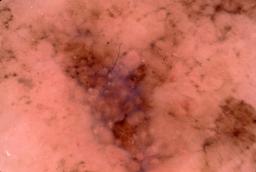

{

"age_approx": 50,

"anatom_site_general": "posterior torso",

"concomitant_biopsy": true,

"dermoscopic_type": "contact non-polarized",

"diagnosis_1": "Benign",

"diagnosis_2": "Benign melanocytic proliferations",

"diagnosis_3": "Nevus",

"diagnosis_4": "Nevus, Atypical, Dysplastic, or Clark",

"diagnosis_5": "Nevus, Dysplastic",

"diagnosis_confirm_type": "histopathology",

"image_type": "dermoscopic",

"lesion_id": "IL_8277002",

"melanocytic": true,

"patient_id": "IP_0549781",

"sex": "male"

}